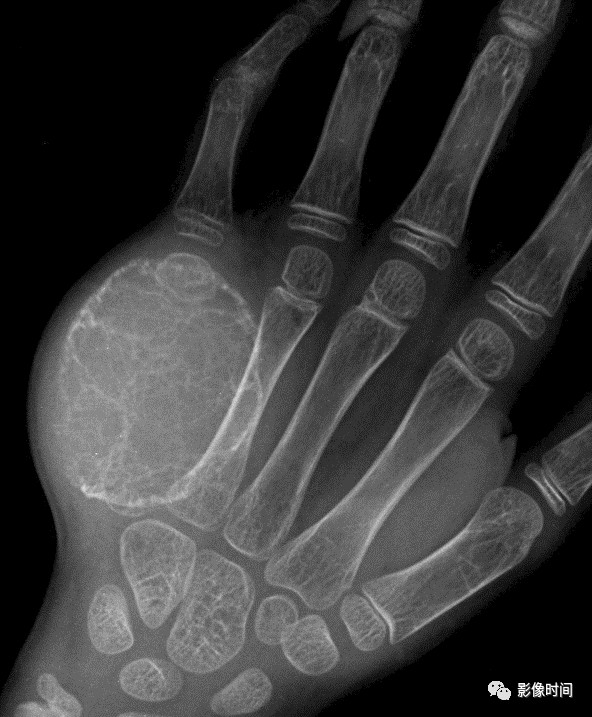

掌指骨常见肿瘤的影像学表现

找到这些影像征象,复杂的骨肿瘤迎刃而解

骨肿瘤的基本影像学征象是构成骨肿瘤最基本的元素,无论多复杂的骨肿瘤都由一个或几个基本影像学征象构成,对其透彻理解和准确把握是正确诊断骨肿瘤的重要前提。